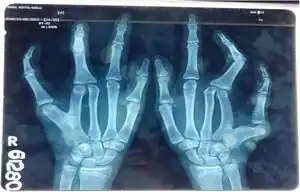

Cenani–Lenz syndactylism is an autosomal recessive congenital malformation syndrome[3][4] involving both upper and lower extremities.

It is characterized by a nearly symmetrical presence of a spoon hand (classical type) or, more frequently, an oligodactylous hand. Individuals with this syndrome present the following symptoms: carpal, metacarpal and digital synostoses, disorganization of carpal bones, numeric reduction of digital rays and toe syndactyly. Additionally, other symptoms may include radioulnar synostosis, brachymesomelia, radius head dislocation, metatarsal synostoses and numeric reduction of rays.